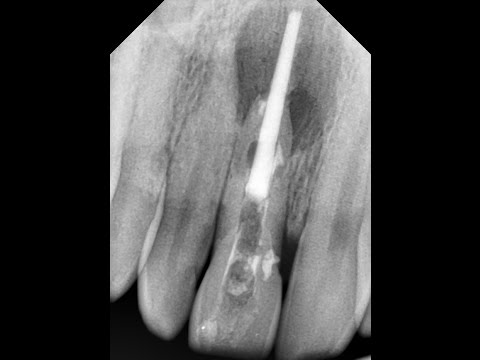

При выходе пломбировочных материалов за верхушку неудачный исход приписывается избыточному материалу. На самом деле, если гуттаперча или обтуратор Термафила вышел за верхушку, значит герметизация апекса неполноценная. Использование конусной гуттаперчи в конусном канале позволит качественно и надёжно запечатывать апикальную часть канала.